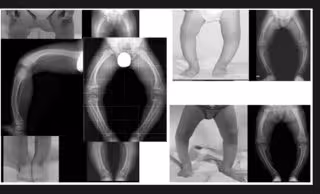

La hipofosfatasia o HPP es una enfermedad ultra rara del metabolismo óseo y mineral caracterizada por un déficit de la actividad de la fosfatasa alcalina no específica de tejido (FANET), debida a mutaciones en el gen codificante de la FANET, lo que da lugar a una hipomineralización esquelética y del cemento dental entre otras manifestaciones clínicas. Esta enfermedad afecta a 1 de cada 100.000 personas en Europa.

Esta enfermedad tiene una alta tasa de mortalidad infantil bien porque los embarazos no llegan a término debido a las malformaciones del feto en el vientre de la madre o porque, una vez que nacidos, estos bebés no llegan a cumplir un año de vida ya que las malformidades de la caja torácica les comprometen órganos vitales como el corazón o los pulmones.